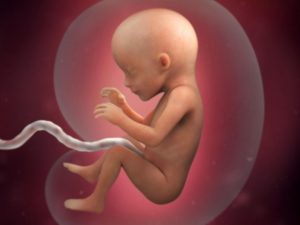

Итак, первые волнения улеглись, наступила 17 неделя беременности, что происходит в этот период с малышом? К этому времени все органы и системы уже сформированы, но они продолжают развиваться и совершенствоваться. Среди наиболее значительных событий, которыми знаменуется 17-ая неделя беременности, стоит отметить:

- Существенным моментом, которым знаменуется развитие плода на 17 неделе беременности – это завершение формирования сердца. Продолжает расти и совершенствоваться система дыхания.

Размер плода на 17 неделе беременности составляет около 11-14 см в длину, а его вес – чуть более 100 граммов. Таким образом, на 17 неделе беременности размер плода можно сравнить с крупной грушей.

Он не просто хаотично двигает руками и ногами, а совершает определенные движения. Он может хвататься рукой за пуповину кувыркаться, плавать, отталкиваясь ногами и руками от стенок матки. Ваш мальчик или девочка обладает выразительной мимикой, он может совершать сосательные и глотательные движения, умеет хмурить брови и строить различные гримасы.

Беременность 17 недель – это срок, к которому плацента уже полностью сформирована, ее вес составляет около 450 граммов.

Плацента представляет собой толстый и плотный слой ткани, который через пуповину связан с плодом. Толщина плаценты в среднем составляет 17 мм. Плацента пронизана разветвленной сетью сосудов, благодаря чему снабжает малыша кислородом и другими необходимыми питательными веществами.